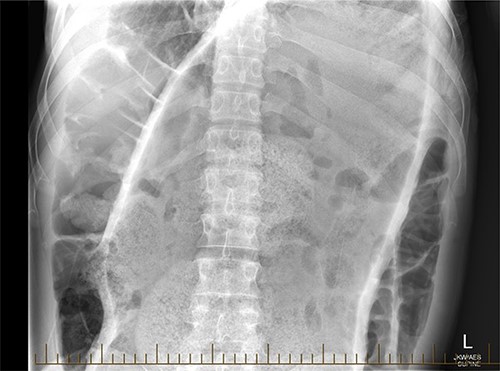

A 28-year-old gentleman self-presented to the emergency department with profuse overflow diarrhea and vomiting. The patient reported he had normal bowel motion until the morning of presentation. He denied any abdominal pain. On examination, the patient appeared pale, diaphoretic and dehydrated. His abdomen was grossly distended, however, was nontender. He was afebrile yet experienced sustained sinus tachycardia to a rate of 120 beats per minute. His blood pressure sat at 96/75 mmHg and was tachypneic to a respiratory rate of 30 and was saturating at 96% on room air. His blood tests showed a leukocytosis to 31, severe metabolic acidosis pH 7.18, lactate 7.7 and hyperkalemia K 6.0 estimated glomerular filtration rate (eGFR) of 68 mL/min/1.73 m2 and a creatinine count of 125μmol/L The computed tomography imaging of his abdomen revealed a massively dilated rectum and sigmoid colon extending to his splenic flexure without evidence of a perforation (Figs 1 and 2). Plain film radiography shows a sizeable faecaloma in the sigmoid colon (Fig. 3).

Coronal view of a CT image of a large faecaloma in the sigmoid.